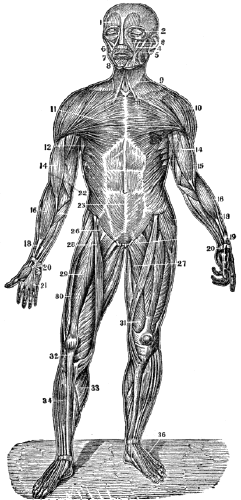

Fig. 2.

Fig. 2. Represents a portion of broken muscular fibre of animal life, (magnified about seven hundred diameters.)